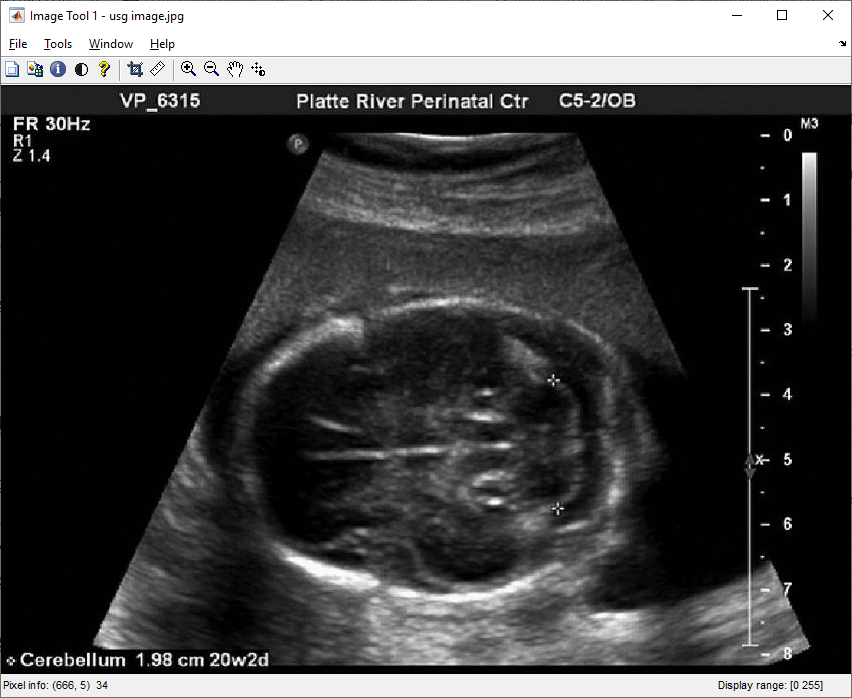

Langkah pertama dalam proses pengolahan citra adalah akuisisi gambar USG yang baik. Pada tahap ini, seorang ahli ultrasonografi mengarahkan transduser ke area kepala janin, menciptakan gambaran gelombang suara yang dipantulkan dari struktur dalam tubuh. Penting untuk memastikan akuisisi gambar yang jelas dan berkualitas untuk memfasilitasi pengukuran yang tepat.

Pertama-tama, source code membaca citra USG dari file ‘usg image.jpg’ menggunakan fungsi imread dan menampilkannya menggunakan imshow. Kemudian, citra dipotong menggunakan fungsi imcrop dengan parameter berdasarkan koordinat dan dimensi yang ditentukan.